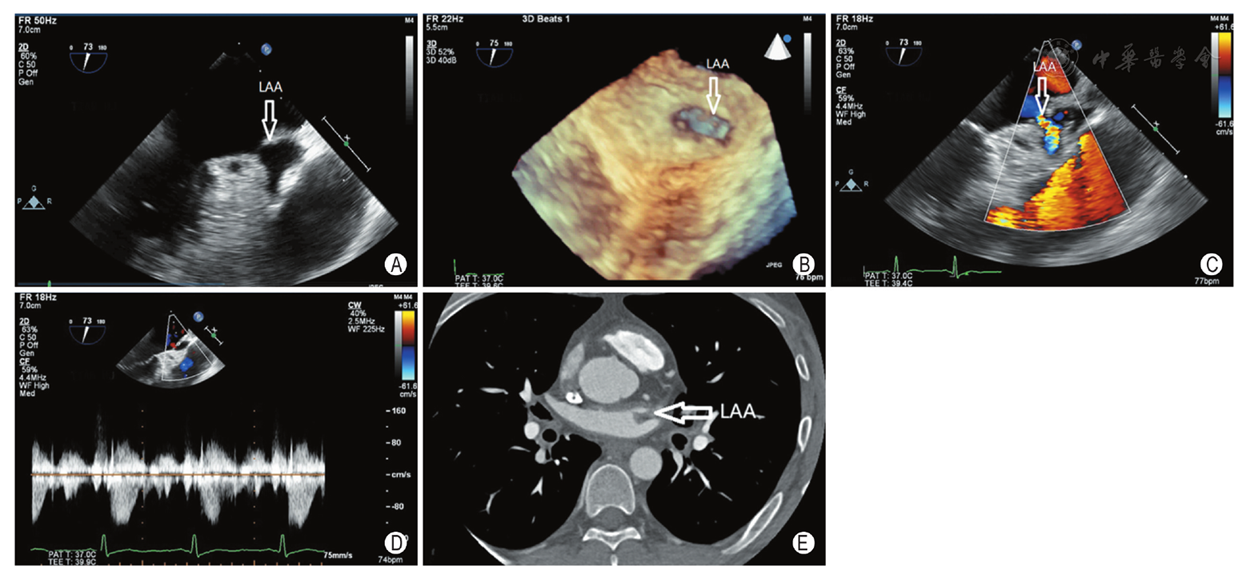

经食管超声心动图诊断孤立性左心耳开口狭窄2例